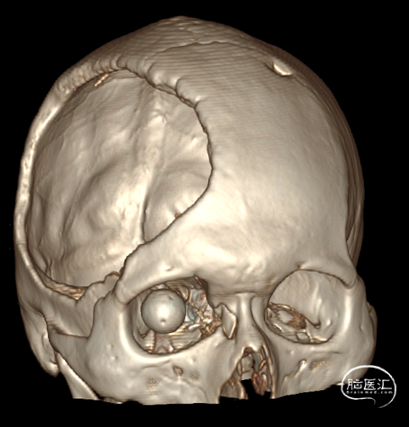

术后即时影像

患者颅内异物已达中颅窝,脑室积血严重

急诊全麻下行右侧额颞大骨瓣开颅+左侧脑室外引流+颅底重建